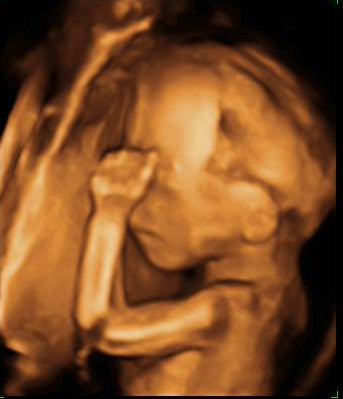

Ecografía 3D de la semana 20: Huesos craneales y del brazo

Se distinguen las fontanelas, imprescindibles para el parto

Esta imagen de una ecografía en 3D en la semana 20 de gestación al feto se le distinguen los huesos de los brazos y del cráneo, así como las fontanelas. Estas son aberturas en los huesos del cráneo que van a permitir que se superpongan cuando el bebé atraviese el canal del parto al nacer.

Bebé de espaldas mostrando el brazo

Si nos fijamos se nota la fontanela y los huesos craneales. También se ven de forma nítida los huesos del brazo: húmero, cúbito y radio.